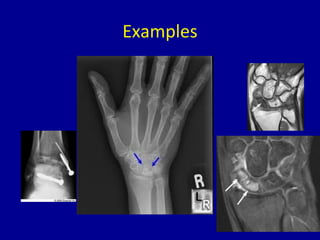

Examples

Bones Affected

• Femoral head – most common by far

• Shoulder – humeral head

• Odontoid (Neck)

• Scaphoid (Wrist)

• Lunate (Wrist)

• Talus (Ankle)